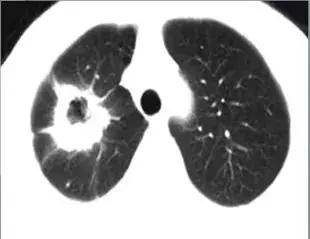

CT征象六:空洞与空腔

空洞(cavity)是肺内病变坏死液化,经引流支气管排除及气体进入而形成的透亮区。

空腔(aircontaining space)是肺内正常生理腔隙的病理性扩大。

空洞(cavity)分型 :

虫蚀样空洞(无壁空洞)

薄壁空洞(≤3mm)

厚壁空洞(>3mm)

疾病:大叶干酪性肺炎

疾病:继发型肺结核

结核球厚壁空洞

肺脓肿厚壁空洞

肺鳞癌厚壁空洞